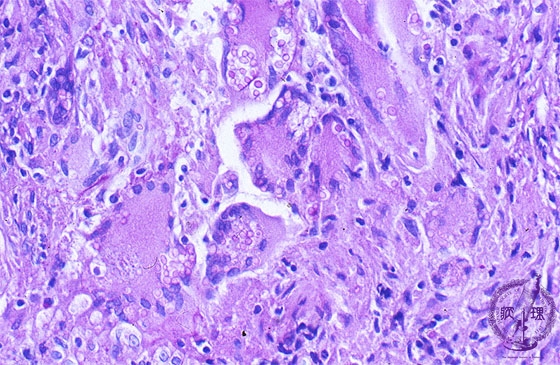

- ★(9)Fungal pneumonia (Cryptococcosis)

Microscopic view (PAS stain, high power view): The mucopolysaccharide membrane of Cryptococcus is red-violet on PAS stain. Unlike to aspergillus, Cryptococcus is a round, yeast-like fungus.